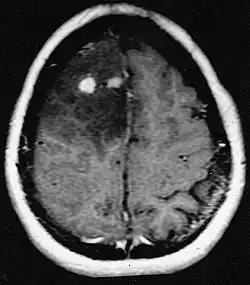

Os pacientes sofrem de uma variedade de sintomas característicos de uma lesão maciça focal ou multifocal. A RM geralmente mostra tumores com realce homogêneo de contraste dentro da substância branca periventricular profunda. Multifocalidade e realce não homogêneo são típicos para pacientes com sistema imunológico enfraquecido. A análise do linfoma do SNC é extremamente importante no diagnóstico diferencial das neoplasias cerebrais. Ressalta-se que a administração de corticosteróides pode levar ao desaparecimento completo do realce, dificultando o diagnóstico das lesões. Consequentemente, se o linfoma do SNC for considerado no diagnóstico diferencial, os corticosteróides devem ser evitados, a menos que o efeito de massa cause um problema sério e imediato no paciente.

As metástases cerebrais são as neoplasias intracranianas mais comuns em adultos, sendo dez vezes mais comuns que os tumores cerebrais primários. Eles pisam em 20 até 40 por cento dos adultos com câncer e estão associados principalmente ao câncer de pulmão e mama e melanoma . Essas lesões resultam da disseminação de células cancerígenas pela corrente sanguínea e ocorrem mais comumente na junção da substância cinzenta e branca, onde a seção transversal dos vasos sanguíneos se altera, aprisionando embolias de células tumorais . 80 por cento das lesões ocorrem nos hemisférios cerebrais, 15 por cento no cerebelo e 5 por cento no tronco cerebral. Cerca de 80 por cento dos pacientes têm história de câncer sistêmico e 70 por cento têm múltiplas metástases cerebrais.

Avanços significativos foram feitos recentemente no diagnóstico e tratamento dessas lesões, resultando em melhora da sobrevida e controle dos sintomas. O início dos sinais e sintomas é semelhante ao de outras lesões maciças no cérebro. O método diagnóstico de escolha é a ressonância magnética com meio de contraste.